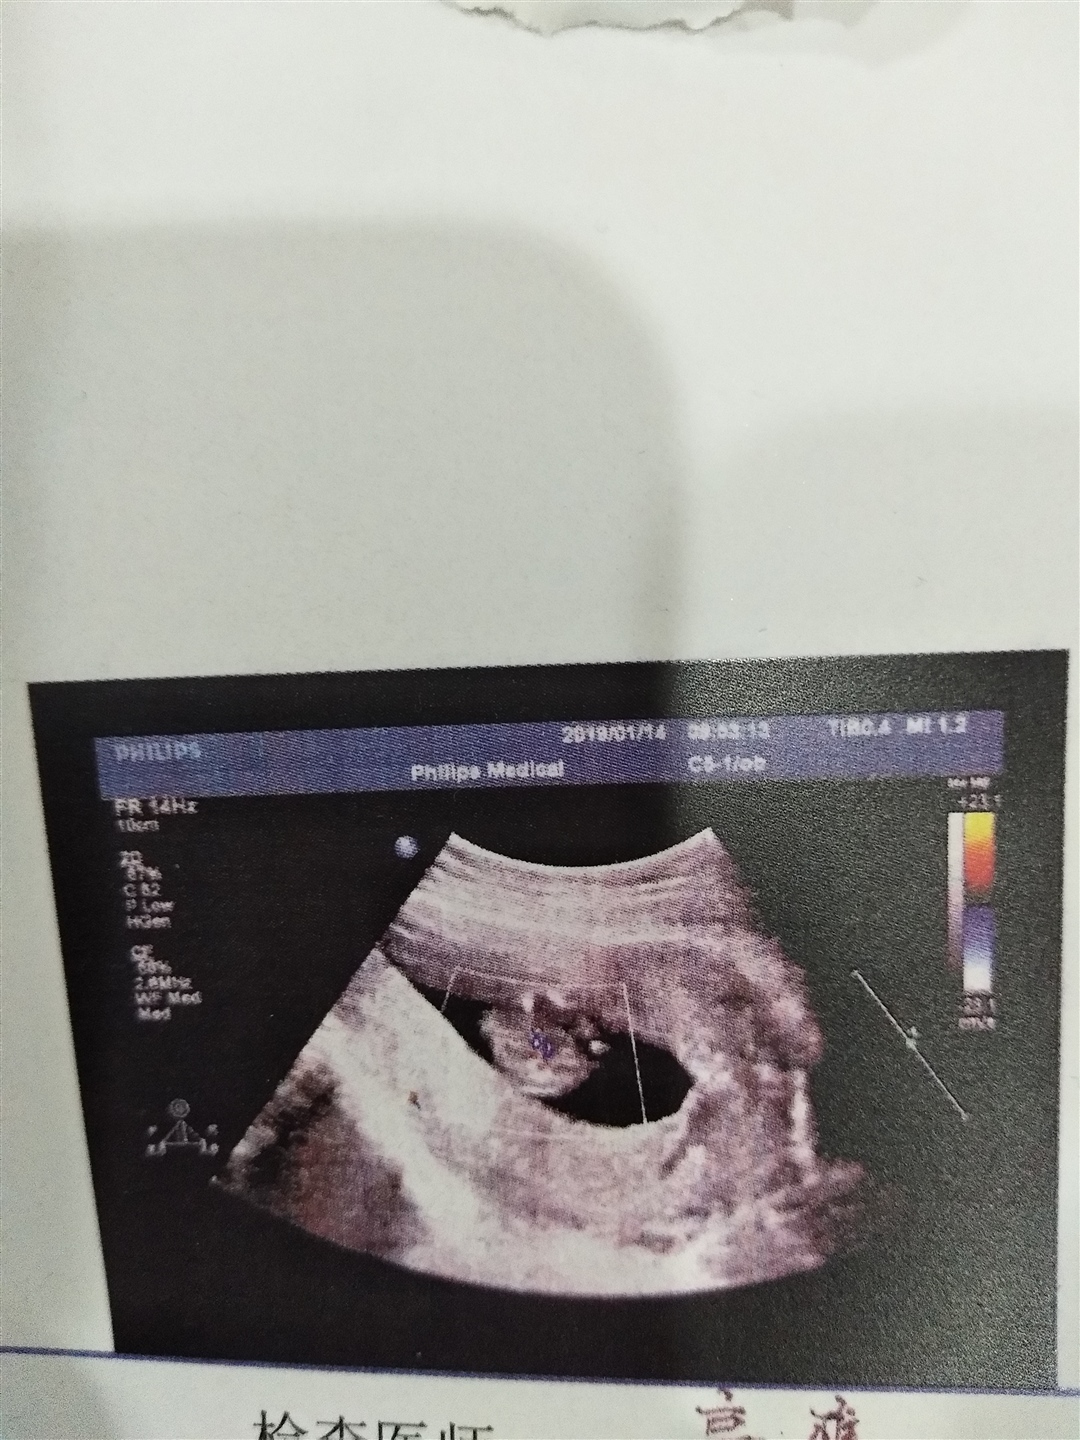

孕3周+6天

女孩几率大,圆形的